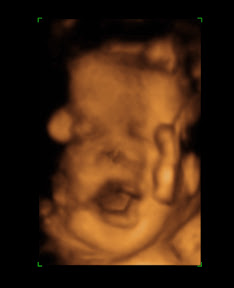

Sebelum myBie gi 'kerja luar' utk kali terakhir sblm saya beranak, kami dah cadang nak wat 3D Ultrasound. Even by dat time, ramai yg tak bagi sbb baby dah tinggal beberapa hari je nak keluar. Doctor pun ckp takyah buat sbb kalau wat 3D Ultrasound, maybe dah tak nampak penuh muka baby sbb dah engaged. Degil le laki bini ni! Nawat jugak! Mmg betul pun, sebahagian kepala baby dah tak nampak..sib bek le still nampak mata, muka, mulut. Yg plg nervous bila gynae kira jari kanan baby.. "1,2,3,4....hmm".

"Let me count it again yeah, 1,2,3,4...hmm(panjang je hmm dia)....ok five". saya:"pwehhh, lega. Syukur Alhamdulillah"